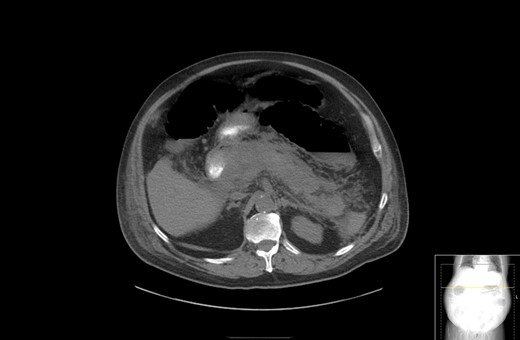

A 67-year-old male presented to his local hospital with postprandial right upper quadrant (RUQ) abdominal pain and vomiting. CT scan of the abdomen and pelvis with oral contrast showed extensive stranding and ill-defined fluid attenuation surrounding his pancreas (Fig. 1). Initial serum amylase and serum lipase levels were 2918 and 17 360, respectively. He was diagnosed with acute, necrotizing, gallstone pancreatitis and developed gastric outlet obstruction (GOO) 9 days after the onset of his symptoms, at which time he was transferred to our institution for further care. On arrival, he had GOO and renal failure (creatinine 2.1 mg/dl). A gastro-jejunal (GJ) feeding tube was placed for jejunal feeds and gastric decompression. On hospital Day 7, the patient’s pain had resolved and a cholecystectomy was attempted laparoscopically, but was converted to open due to inflammation around the infundibulocystic junction. Subsequently, a follow-up contrasted CT showed marked interval necrosis of pancreatic tissue resulting in numerous lobulated soft tissue and gas collections in the upper abdomen, midline upper pelvis, and in the gallbladder fossa (Fig. 2). A pancreatic drain was placed by interventional radiology (IR) on hospital Day 20 for interval increase in pancreatic necrosis on CT. On hospital Day 23, IR embolization of gastroduodenal artery (GDA) was performed due to GI bleeding. Laparoscopic necrosectomy with malencot drain placement was performed on hospital Day 36. Post-operatively, he had a large upper GI bleed requiring emergent endotracheal intubation and initiation of the massive transfusion protocol. Angiography was performed and was negative. On the following day, hospital Day 39, GI performed an EGD and found hemorrhagic gastritis, but no localizable bleeding. He was placed on high dose PPI, carafate and octreotide. He progressed to acute renal failure with initiation of hemodialysis on hospital Day 45. On hospital Day 47, a follow-up EGD was done with exchange of the gastrojejunostomy tube, and hemorrhagic gastritis was still present. He was transferred to the general surgery inpatient unit the following day. On hospital Day 54, he developed another upper GI bleed requiring ICU transfer. EGD was again performed and the hemorrhagic gastritis remained, but no active site of bleeding was identified. On hospital Day 56, a second look EGD was done with similar findings of hemorrhagic gastritis with no identifiable active bleeding. On hospital Day 58, the patient elected to receive palliative care rather than undergo subtotal gastrectomy. He died 9 days later at home.

CT with contrast showing marked interval necrosis of pancreatic tissue.